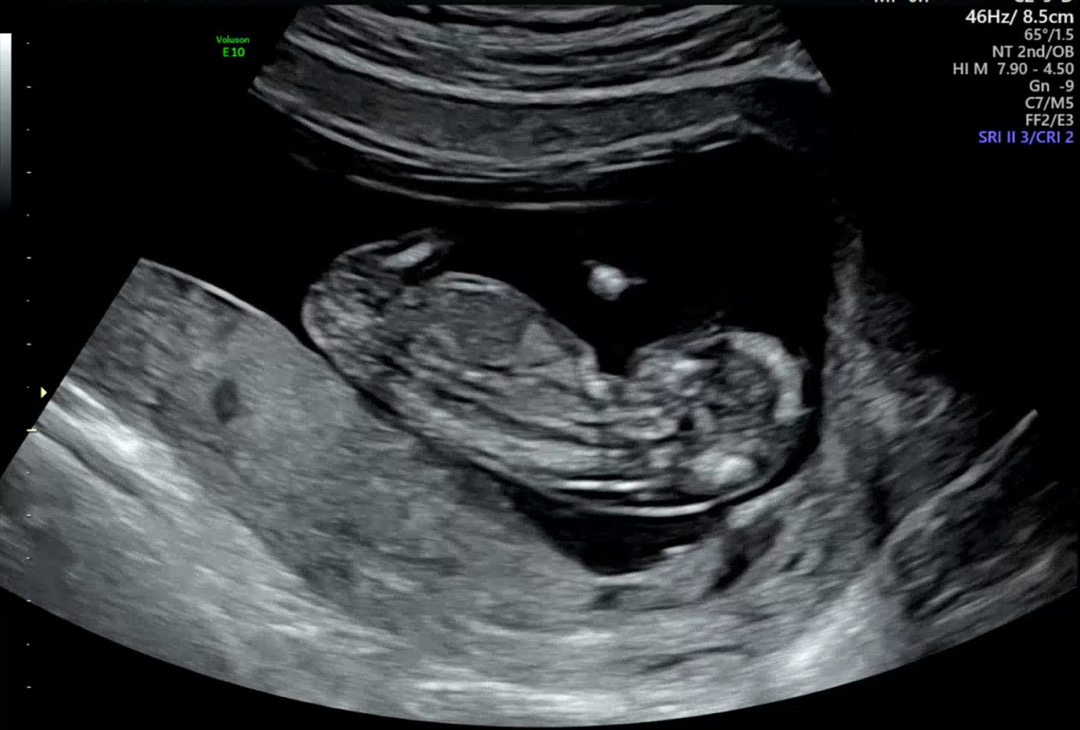

12주 3일 각도법 봐주실 수 있나용!!

각도법을 어떻게 보는지 ㅎㅎ 모르겠어서 올려봅니당!! 성별이 보이나요.. ㅎㅎ